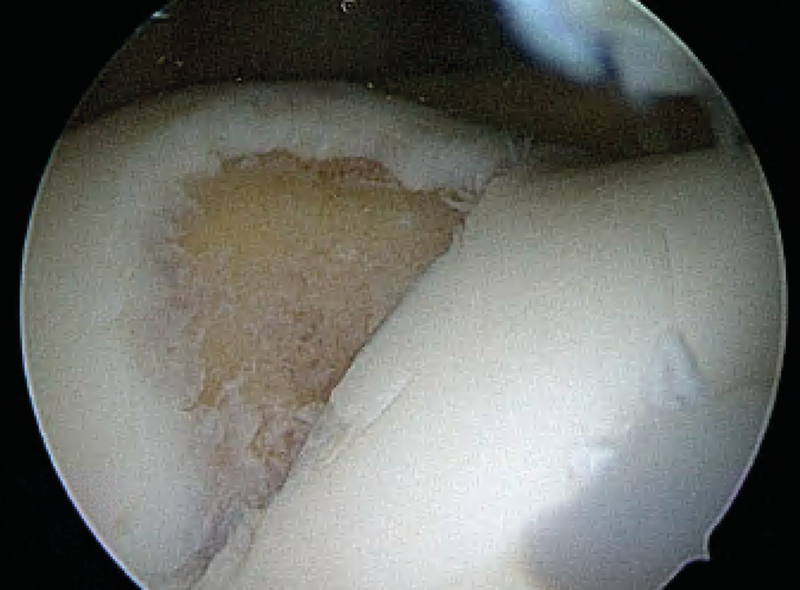

Autologous chondrocyte chips (Minced Cartilage - MC)

The defect size is documented via an arthroscopy, as with all previous procedures. The chondrocytes can also be harvested by arthroscopy with a collection container fitted between the shaver attachment. It is currently being discussed whether this results in undesirable excessive damage to the chondrocytes. To circumvent this, the cartilage fragments can also be collected in an open procedure and manually chopped with the scalpel. Well preserved cartilage fragments from the defect and non-weight bearing points (i.e. notch roof) are suitable harvest sites (Fig. 28, 29). In particular, it must be ensured during the arthroscopy procedure that only well-preserved cartilage tissue is harvested and not contaminated by other soft tissue (Synovia, Hoffa etc.).

The harvested paste-like chondrocyte mass can be enriched with platelet rich plasma (PRP) or platelet rich fibrin (PRF) (Fig. 30), which is centrifuged from the patient’s whole blood during the surgery (Fig. series 31).

The produced cell mixture is then introduced into the defect and stabilised with fibrin glue (Fig 33). In addition, the product can be secured by a membrane against shear forces, as in the AMIC procedure and stabilized with fibrin glue or sutures. In the current trial phase further different combinations of the “minced” technique are being tested, although microfracture surgery or microdrilling may also be additionally performed.